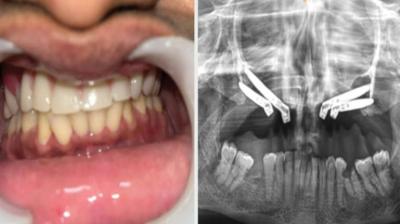

24 वर्षीय युवती के चेहरे पर लौटी मुस्कान और आत्मविश्वास

6 Sep, 2025 10:00 PM IST | LIONNEWS.IN

एम्म में जटिल सर्जरी को सफलतापूर्वक अंजाम दिया है। इस सर्जरी में ट्यूमर के कारण काटे गए निचले जबड़े को पैर की हड्डी से दोबारा बनाया गया और उसमें 13...